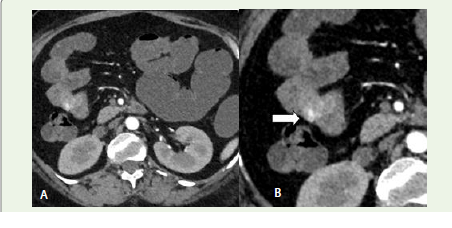

Figure 2:Axial section (Early arterial phase) and Zoomed image on

left: Reveals increased intra-luminal attenuation within the jejunum that

was absent on pre-contrast images—consistent with active contrast

extravasation. This pattern of high-attenuation foci in post-contrast images

not present in earlier phases confirms ongoing bleeding [1].